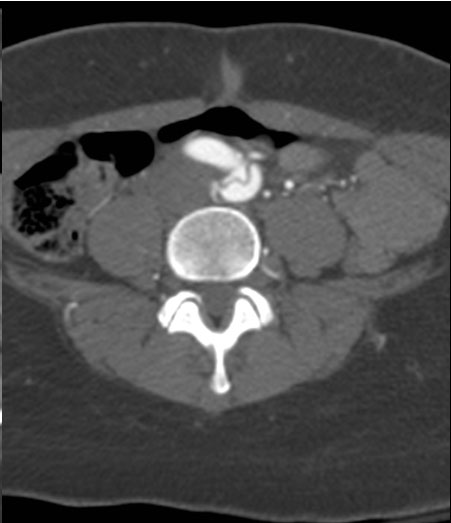

A 49-year-old woman with a history of hypertension and smoking presented to an outside hospital with sudden onset chest pain and hypotension. Computed Tomography/ Angiography (CTA) of the chest and abdomen revealed a type A aortic dissection extending from the ascending aorta to the left common iliac artery. (Figure 1) Of note, there was a significant pericardial effusion and left pleural effusion. Due to her hypotension and tamponade physiology, the patient was rapidly intubated followed by unsuccessful pericardiocentesis. The patient was then transferred to our institution for emergent dissection repair.

Figure 1a-e. Computed Tomography/Angiography (CTA) at

presentation demonstrating a type A aortic dissection.

Figure 1a. Axial CT at level of the pulmonary artery. The false lumen in the ascending aorta (white arrow) has minimal flow.

Figure 1b.

Figures 1b-d. Axial CT cuts demonstrating the dissection continuing into the left common iliac artery.

Figure 1e. Oblique sagittal CT reconstruction demonstrates the Type A dissection is complex with multiple fenestrations in the abdomen. Note bovine arch anatomy.